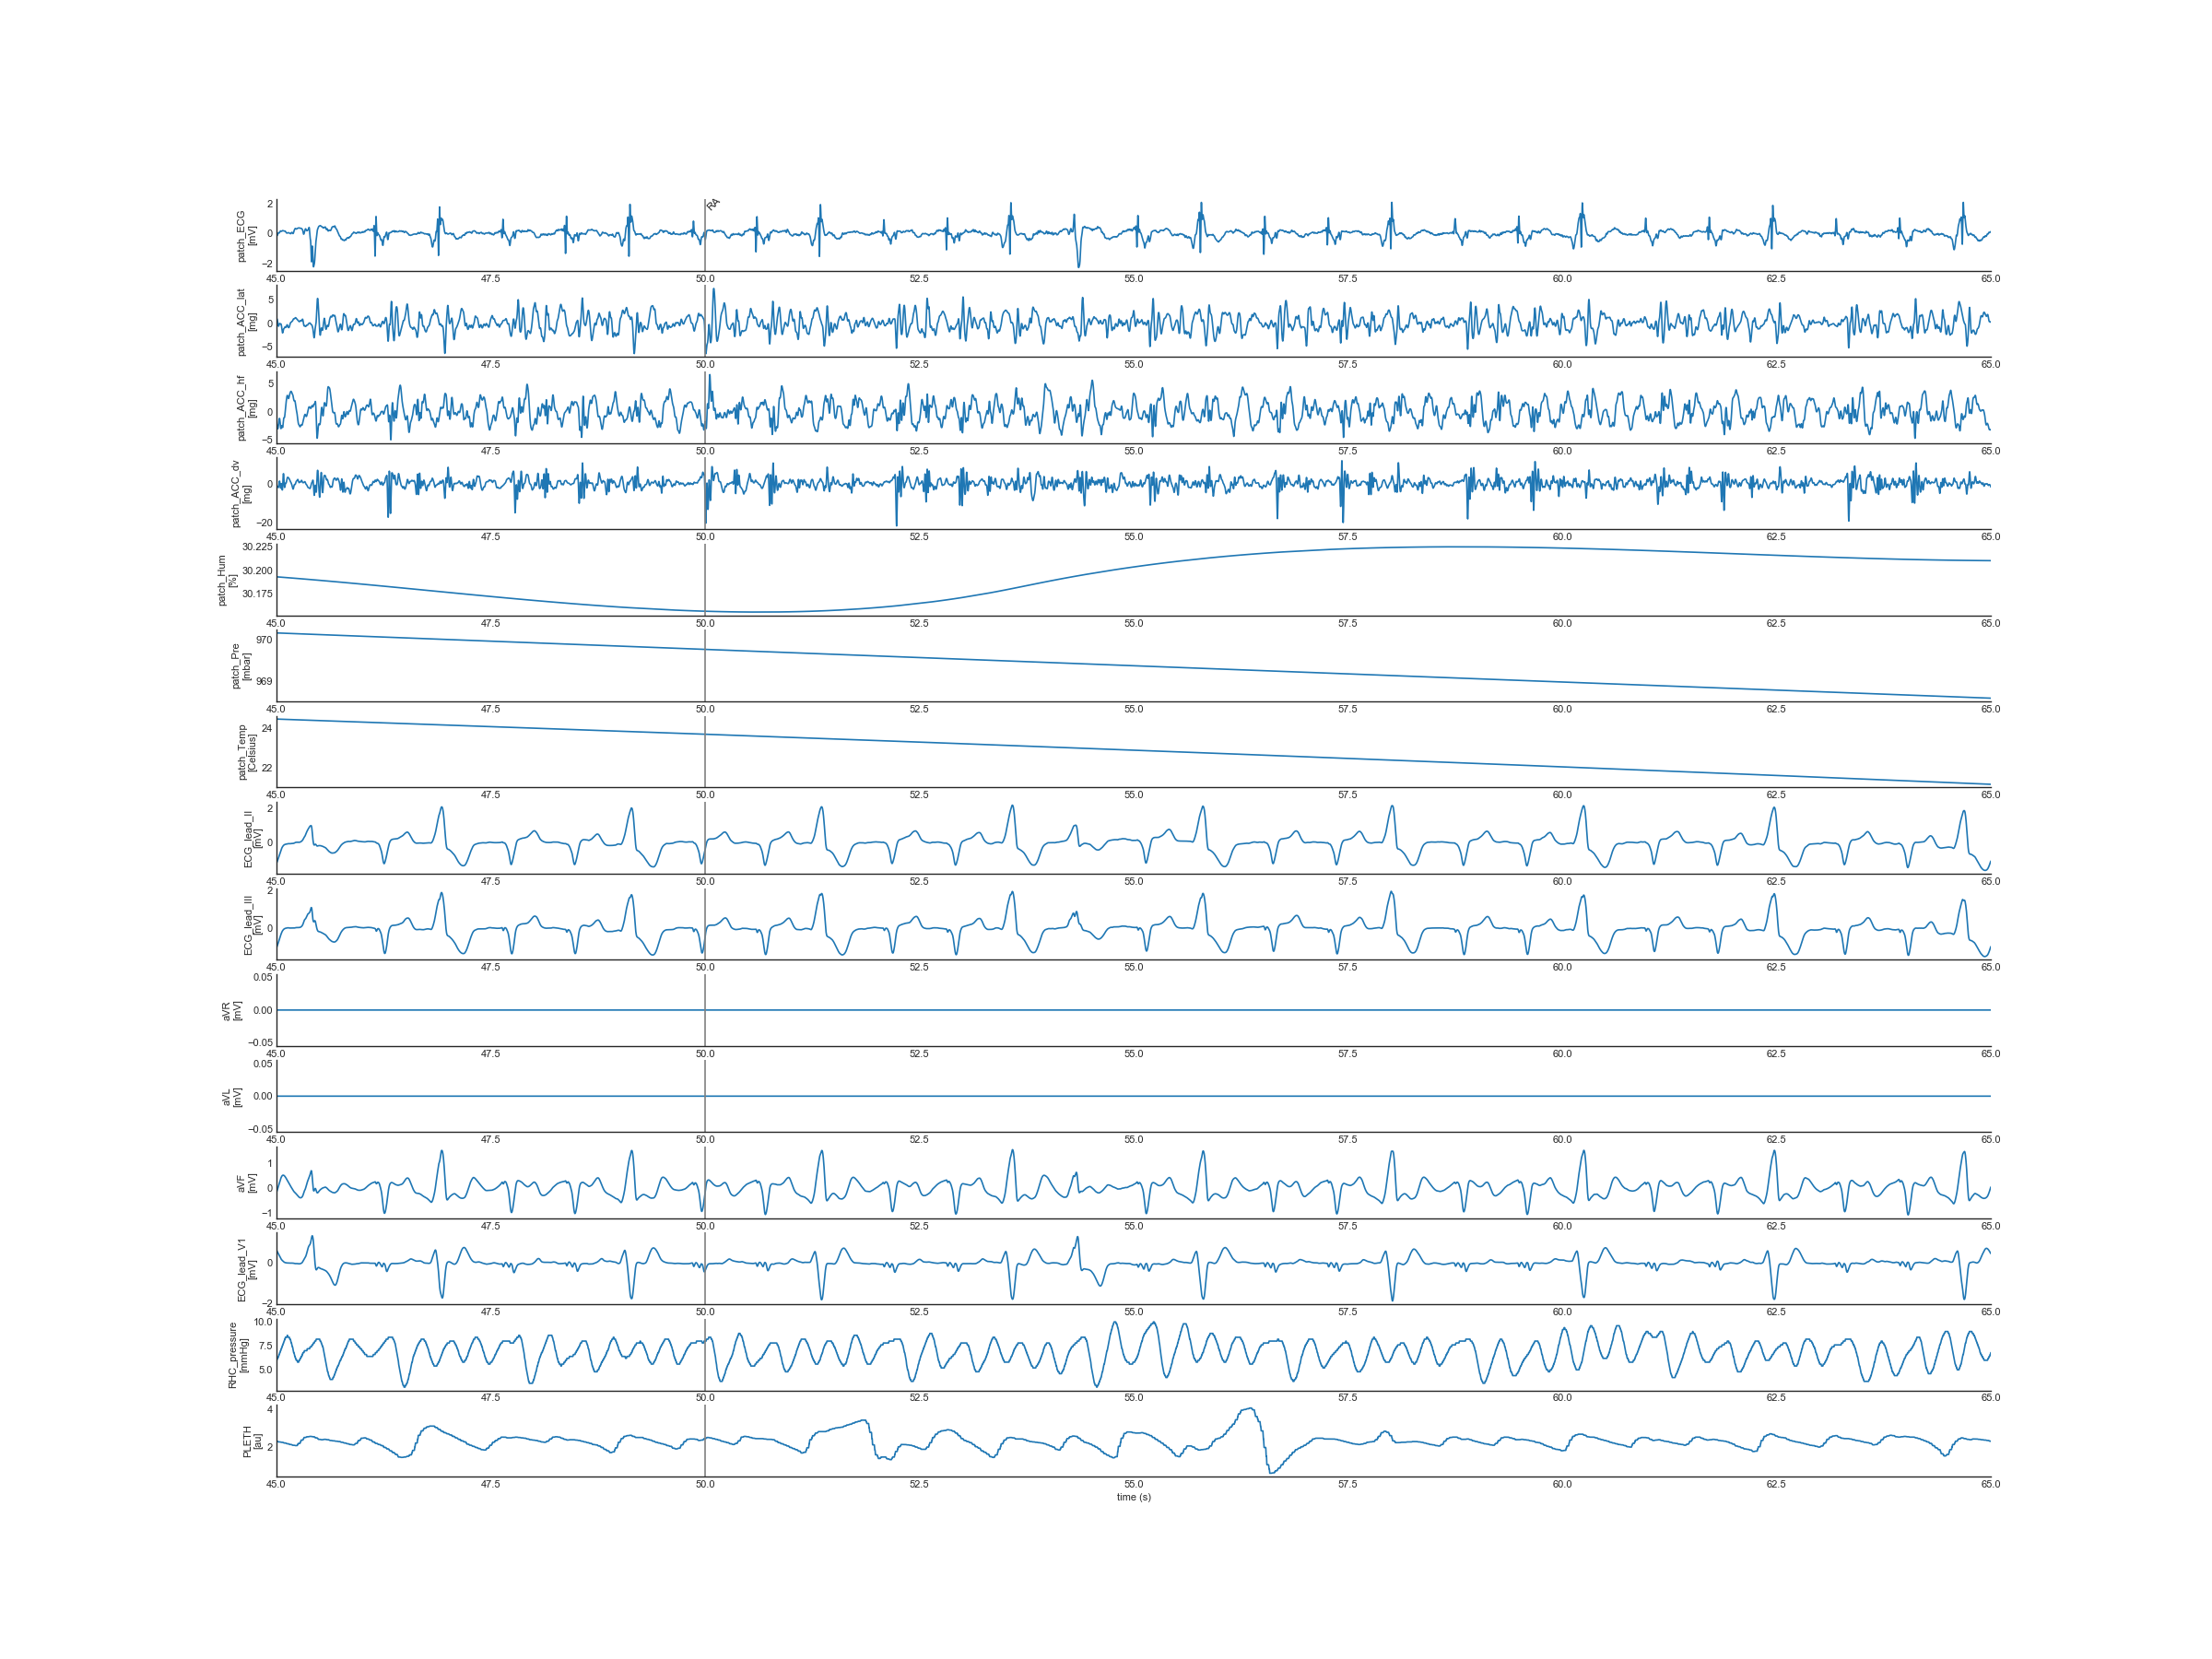

Contents in signal preview

In this folder, plots are provided to help users quickly preview the quality of the data are provided. Three different windows of the WFDB signals are plotted for all subjects:

• /FirstChamber_20s: shows the WFDB signals 5s before and 15s when RHC first entered a chamber.

• /full: shows the full recording of the WFDB signals

• /random_20s: shows a randomly selected 20s window of the WFDB signals

Signals in the dataset recorded by the wearable patch (stored in the WFDB format: TRMXXX-RHCY.dat)

• Patch_ECG: ECG signal measured by the patch (unit: mV)

• Patch_ACC_lat: ACC signal in the lateral direction measured by the patch (unit: mg)

• Patch_ACC_hf: ACC signal in the head-to-foot direction measured by the patch (unit: mg)

• Patch_ACC_dv: ACC signal in the dorsal-ventral direction measured by the patch (unit: mg)

• Patch_Hum: Humidity signal measured by the patch (unit: %)

• Patch_Pre: Ambient pressure measured by the patch (unit: mbar)

• Patch_Temp: Skin temperature measured by the patch (unit: Celsius)

Note that SCG signals can be extracted using a [1, 40] Hz bandpass filter.

Signals in the dataset recorded by Mac-Lab (also stored in the same WFDB file: TRMXXX-RHCY.dat)

• RHC_pressure: RHC blood pressure recorded by Mac-Lab (unit: mmHg)

• ART: Arterial blood pressure recorded by Mac-Lab using arterial line (unit: mmHg)

• ECG_lead_I: Lead I ECG recorded by Mac-Lab (unit: mV)

• ECG_lead_II: Lead II ECG recorded by Mac-Lab (unit: mV)

• ECG_lead_III: Lead III ECG recorded by Mac-Lab (unit: mV)

• aVR: Augmented Vector Right ECG recorded by Mac-Lab (unit: mV)

• aVL: Augmented Vector Left ECG recorded by Mac-Lab (unit: mV)

• aVF: Augmented Vector Foot ECG recorded by Mac-Lab (unit: mV)

• ECG_lead_V1: V1 pericordial lead ECG recorded by Mac-Lab (unit: mV)

• PLETH: Plethysmogram signal recorded by Mac-Lab using pulse oximeter sensor (unit: a.u.)

• RESP: Respiratory signal recorded by Mac-Lab (unit: a.u.)